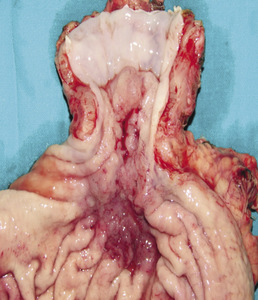

Zgodnie z definicją rozpoznanie raka połączenia przełykowo-żołądkowego wymaga spełnienia dwóch kryteriów: topograficznego i histopatologicznego. Pierwotne ognisko nowotworu powinno być umiejscowione w polu anatomicznym sięgającym 5 cm powyżej i poniżej zdefiniowanego endoskopowo wpustu żołądka (czyli pola między linią Z, wytyczającą miejsce przejścia nabłonka płaskiego przełyku w nabłonek gruczołowy, a początkiem fałdów żołądkowych). Histologicznie nowotwór jest rakiem gruczołowym. Powszechnie przyjęta klasyfikacja zaproponowana przez Siewerta opiera się na topograficznej lokalizacji raka (ryc. 1).6

Typ I odpowiada zmianie umiejscowionej pierwotnie w dolnym odcinku przełyku (od 1 do 5 cm powyżej wpustu). Rozwija się on zazwyczaj na podłożu metaplazji jelitowej (przełyk Barretta) i nacieka połączenie przełykowo-żołądkowe. Typ II, uznawany za prawdziwego guza wpustu (do 1 cm powyżej do 2 cm poniżej wpustu), rozwija się na podłożu nabłonka wpustu lub tzw. krótkiego segmentu metaplazji jelitowej. Typ III to pierwotnie guz podwpustowy (od 2 do 5 cm poniżej wpustu) naciekający połączenie przełykowo-żołądkowe (ryc. 2).